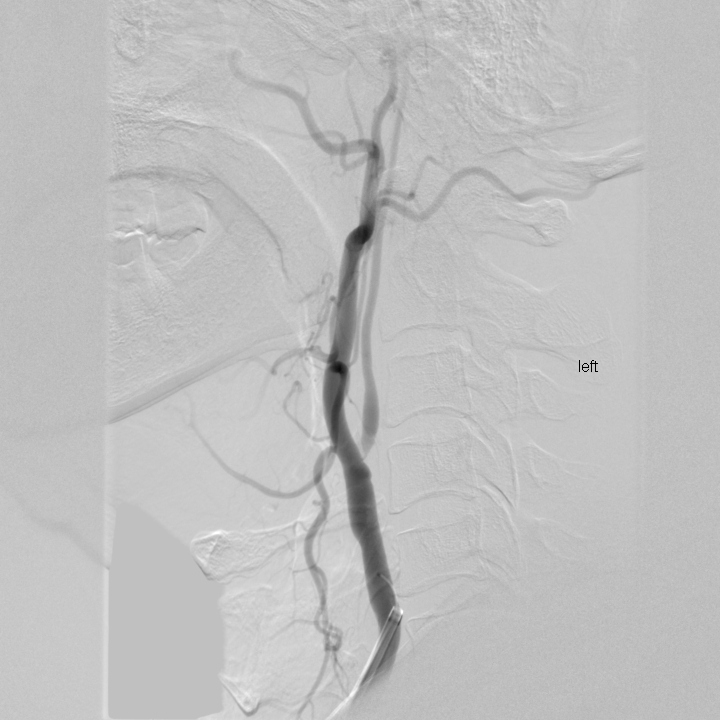

急性下肢動(dòng)脈缺血

治療前

治療后